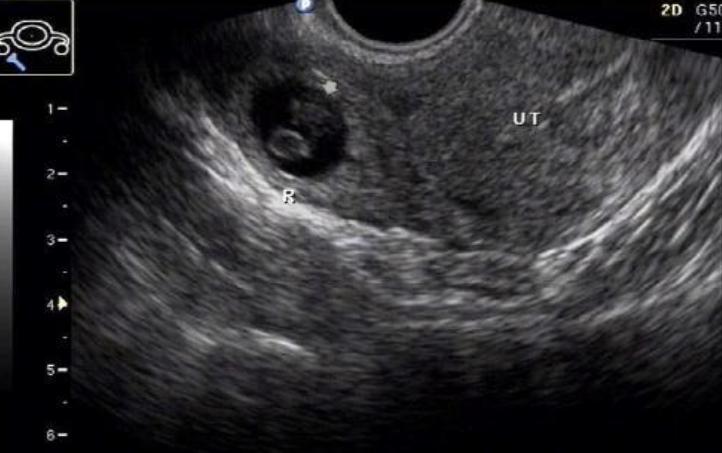

筛查包括通过超声波检查确认胚胎是否在子宫内着床,以及检查输卵管通畅性。